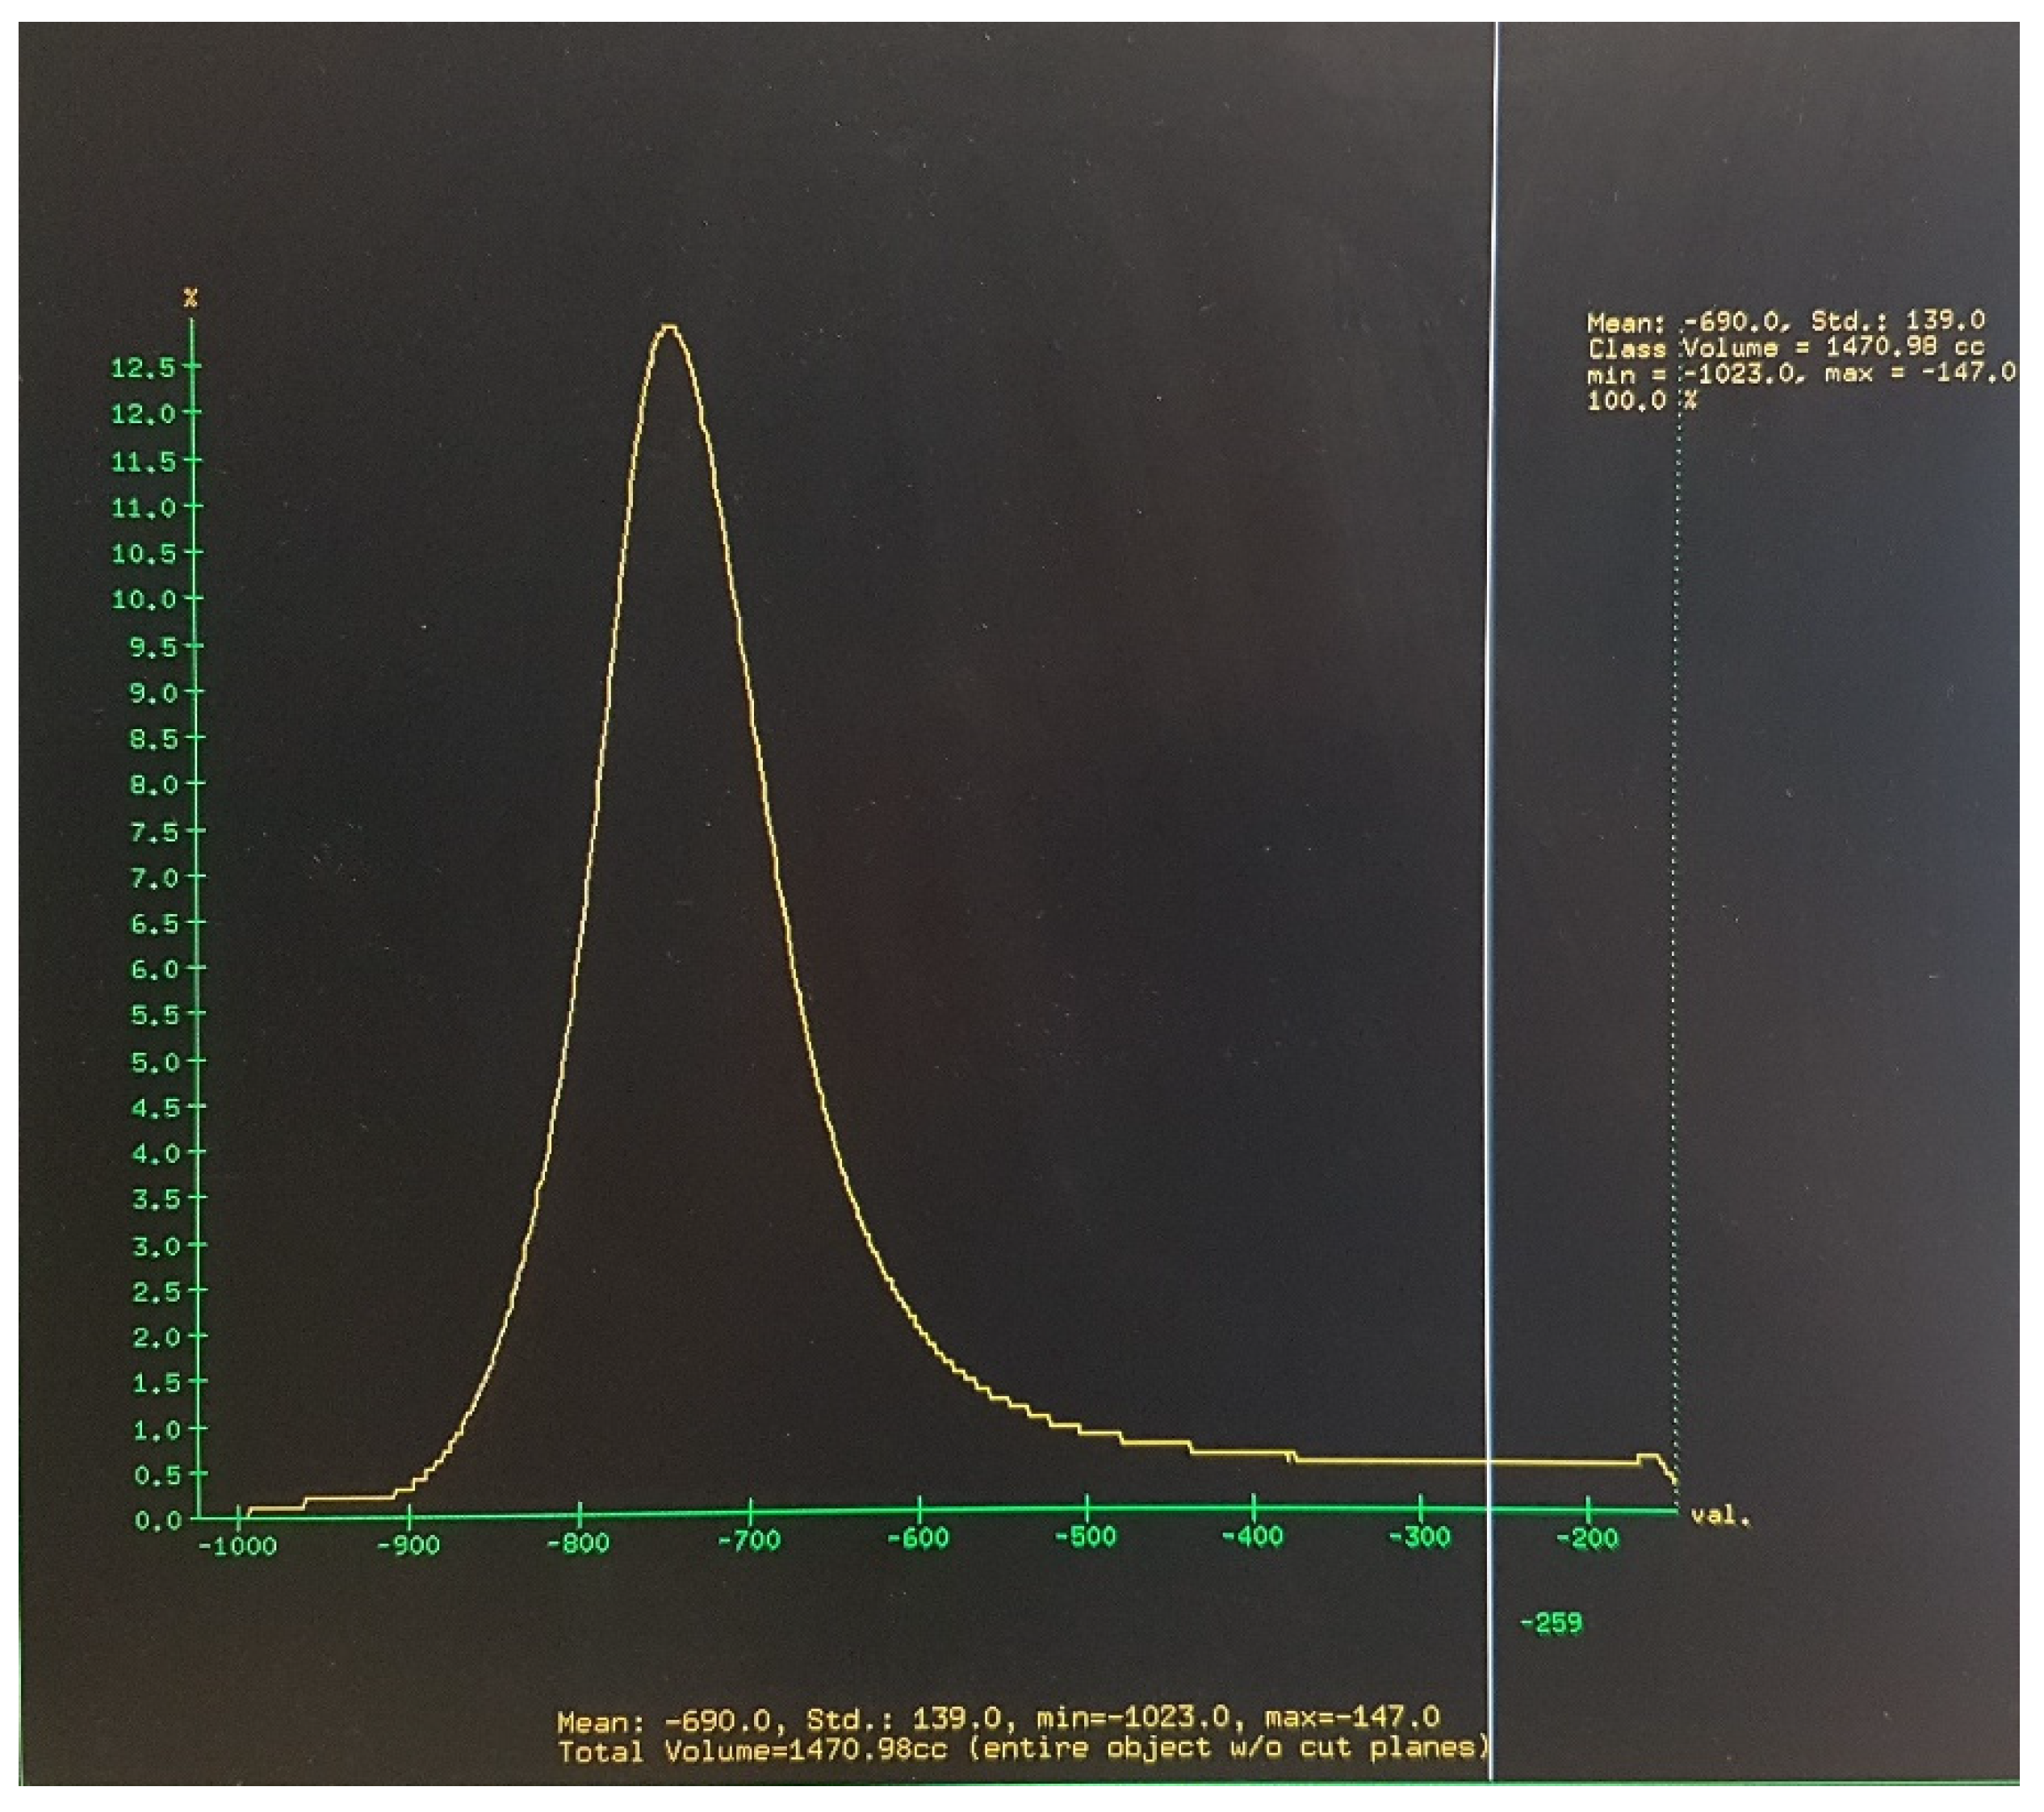

2.2. Image Acquisition, Analysis, and Definition of Attenuation Thresholds

2.3. Outcome Measures and Data Analysis

3.3. Age-Dependence of Low and High Attenuation Thresholds